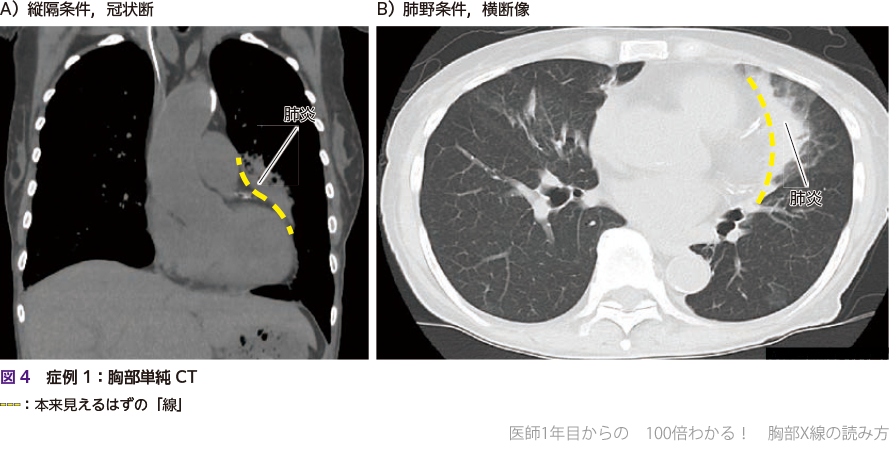

胸部のCT 胸部CT検査 | 呼吸器の検査 | 各検査を知る | 人間ドック | 健診の詳細情報

胸部CT検査 | 呼吸器の検査 | 各検査を知る | 人間ドック | 健診。CT装置のご紹介 | こうのす共生病院|埼玉県鴻巣市。胸部CT | 画像診断検査 | 各検査を知る | 人間ドック | 健診会。医師解説】胸部CT検査の基本とCT写真の見方完全ガイド(※言い。「胸部のCT」村田 喜代史 / 上甲 剛 / 村山 貞之定価: ¥ 15000#村田喜代史 #村田_喜代史 #上甲剛 #上甲_剛 #村山貞之 #村山_貞之 #本 #自然/医療・薬学・健康裁断済み中身は未使用に近い